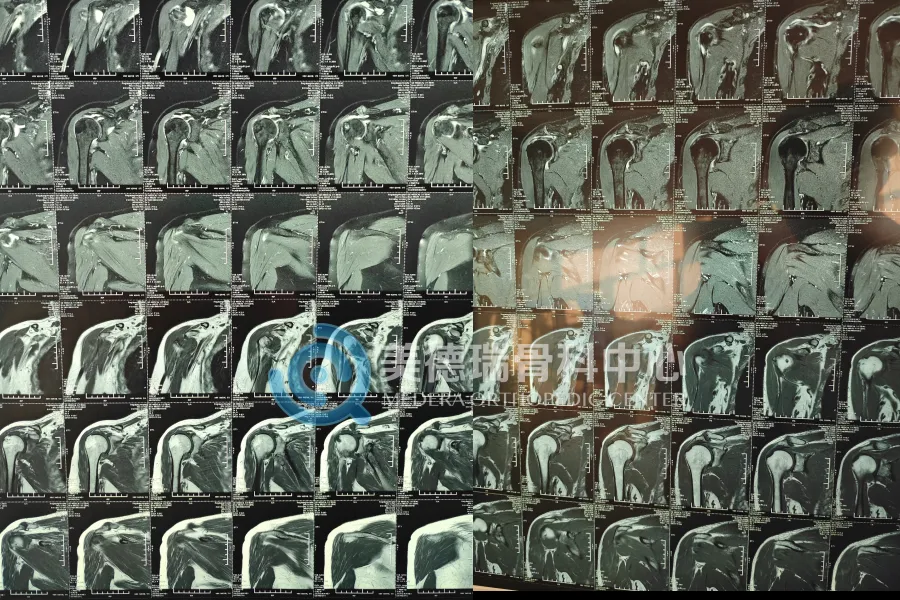

最近,平庄矿区医疗集团总医院美德瑞骨科中心在常态化开展肩关节镜治疗的基础上,又连续完成两例此类手术:右肩肩峰成形术 + 肩袖修补缝合术。手术由中心北京长驻专家团队协作完成。两位患者术后疼痛均明显减轻,肩关节活动度在康复训练中逐步改善,目前恢复进展平稳。

第一位患者属于门诊里常见的一类:右肩疼,活动受限,影像提示肩袖损伤合并肩峰撞击。这类问题最大的坑,是“凑合着用”。能忍就忍、能贴就贴、能理疗就理疗,短期能缓一缓,但不少人会越拖越不敢用那只手,力量下去、活动范围更小,最后还是得面对治疗选择。

第二位患者更麻烦:确诊为巨大肩袖撕裂。撕裂范围大、组织状态更差,修补时对关节镜下的操作精细度要求更高,处理不好,后面的功能恢复就容易受影响。

手术中,专家团队在高清关节镜辅助下完成肩峰减压与成形,并对肩袖撕裂组织进行清理、复位与缝合固定。术后两位患者均反馈:疼痛已经开始缓解,动作也开始一点点回来了——尤其是抬举动作,比之前更容易做到。后续康复由医护团队指导推进,节奏按阶段走,避免“太着急练”或者“完全不敢动”这两种常见误区。